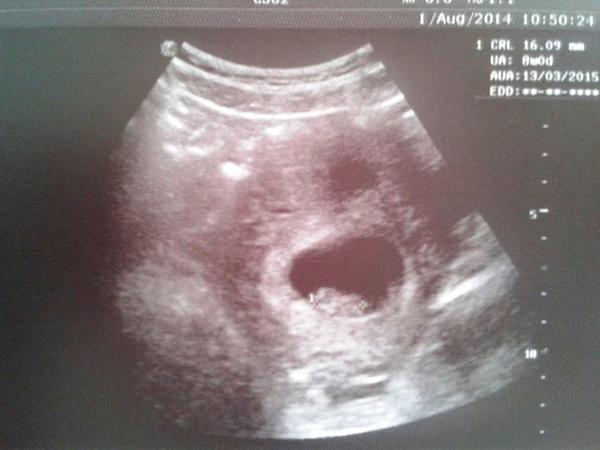

Mimi je v pořádku, odpovídá 8+4tt, srdíčko buší jak zvon 😀. Příští týden si jdu pro průkazku a na první odběry. Moje nová Dr. mě pro jistotu poslala na prvotrimestrální screening do Gennetu, právě jsem se objednala.

Moc děkuju za podporu, byla jsem tak vystresovaná, že jsem se při UTZ sesypala a brečela jak malá - úlevou, radostí. Nemám tu bolestnou zkušenost stále v sobě zpracovanou, dnes to opět vyplulo...

Přikládám fotku z UTZ, ne proto, abych se chlubila, ale abych byla vám ostatním nadějí 🙂.